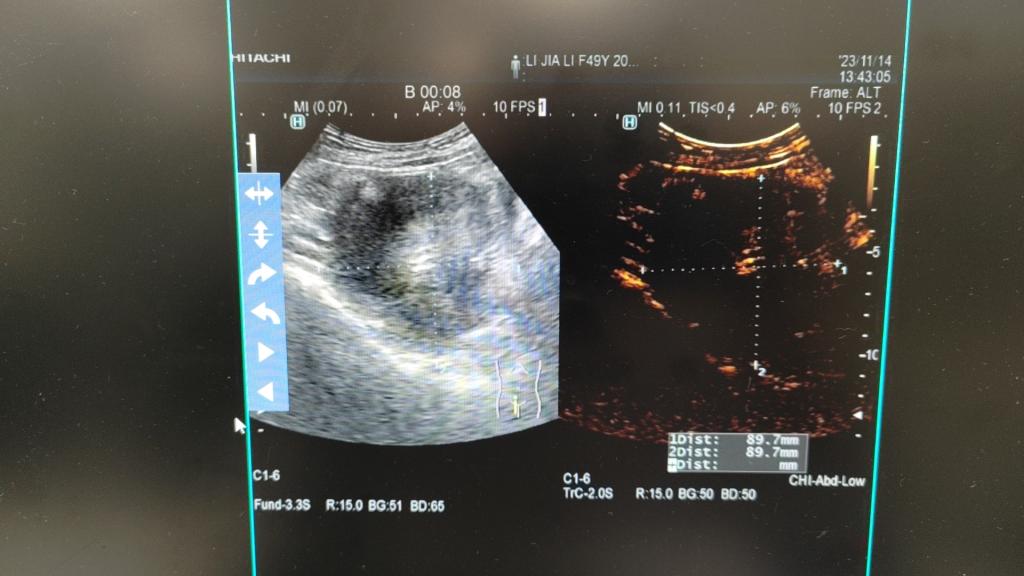

2023年11月14日,我院妇科二病区主任梁月秀带领团队,在麻醉科覃福兴医师、超声科专家利青及麻海智医师的协作下,在全身麻醉下为患者成功施行了超声引导下人工腹水+超声引导下宫颈病灶微波消融术+宫颈病灶穿刺活检术+宫颈病灶穿刺注射聚桂醇硬化治疗。术中,我院妇科二病区梁月秀主任团队运用娴熟的操作技术,在超声引导下合理选择手术入路,将微波消融针直接穿刺到病变部位,对患者病灶进行了多点位消融灭活,由消融针释放的热磁场可以使周围的分子高速旋转运动并摩擦升温,从而使消融区组织发生不可逆凝固性坏死,使病灶缩小或逐渐消失,达到治疗的目的。消融后,梁月秀主任团队再次用超声造影即刻评估消融灶无血供区达到预期,准确迅速地完成了此例次全子宫切除术后宫颈病灶微波消融术。

消融后,我院妇科二病区梁月秀主任团队再次用超声造影即刻评估消融灶无血供区达到预期,准确迅速地完成此例次全子宫切除术后宫颈病灶微波消融术